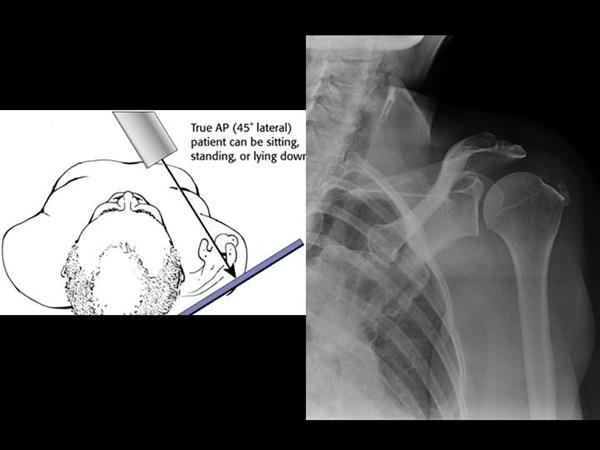

2. True shoulder AP

Glenohumeral joint space, DJD, and proximal migration of humerus